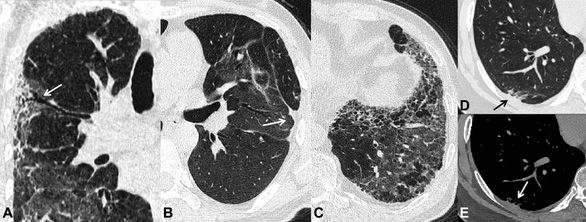

Những di chứng sau viêm phổi do SARS-CoV-2 được ghi nhận trên phim CT scan ngực sau 6 tháng theo dõi. A-giãn phế quản co kéo (mũi tên). B- xẹp phổi dạng đường (mũi tên). C- xơ phổi dạng tổ ong. D và E- dày màng phổi tạng (mũi tên)

Trên phim chụp CT scan ngực, hình ảnh xơ hóa phổi biểu hiện dưới nhiều dạng và mức độ như: hình ảnh dải xơ, dày các vách liên tiểu thùy, hình ảnh lưới, giãn phế quản co kéo và điển hình nhất là hình ảnh tổ ong